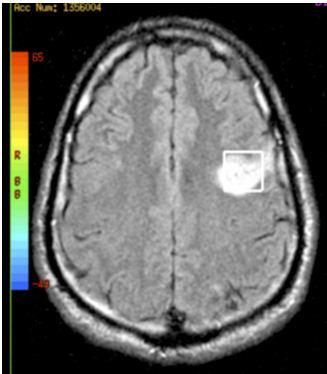

A 42-year-old man presented after multiple episodes of difficulty in speaking. MRI of the brain without contrast suggested an acute infarct in the left frontal supraventricular white matter. Subsequent MRI with contrast indicated a subacute infarct. MRI spectroscopy verified an ischemic infarct. The patient underwent transesophageal echocardiography, seen here, that showed a patent foramen ovale (PFO). The diagnosis was cryptogenic ischemic stroke. Approximately 40% of cryptogenic ischemic strokes are attributed to PFO.

Image courtesy of Seema Tayal, MD, MBA; Apar Bains, MD MPH; Phillip Telefus;

Irina Erlikh, MD; and Vasantha K. Kondamudi, MD.